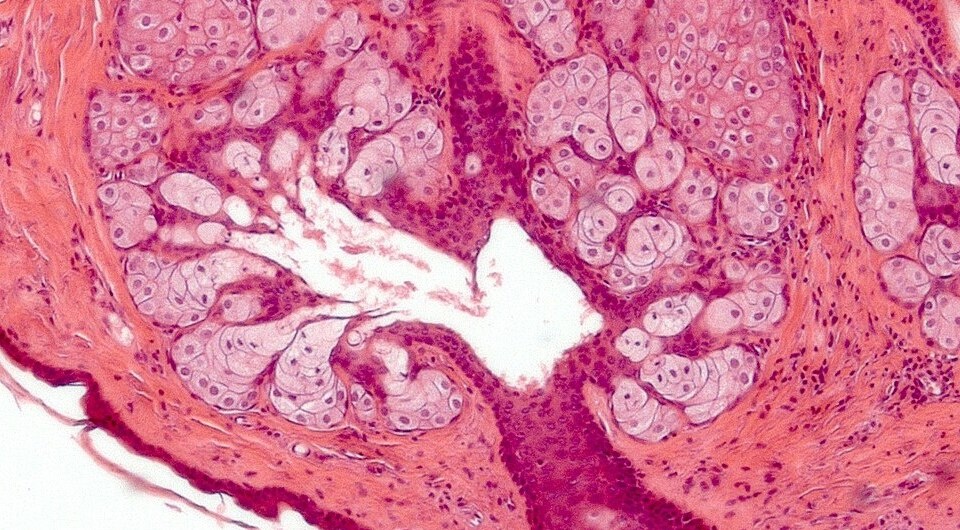

Pathologist without beard / Wikimedia Commons, CC-BY-4.0